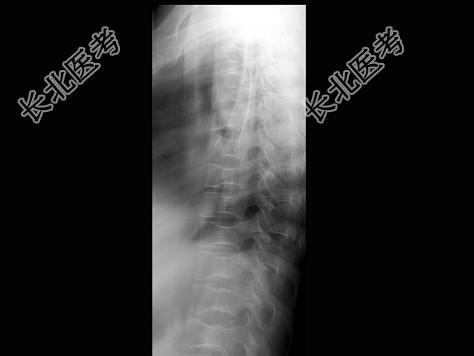

- 单项选择题女,24岁, 反复发作的骨骼肌肉痛,结合图像, 最可能的诊断是 ( )

A、镰状细胞贫血

B、地中海贫血

C、骨梅毒

D、白血病

E、椎间盘突出